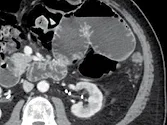

Figure 9. Métastases hépatiques d’un cancer du colon. Récidive après résection

chirurgicale traitée par association contenant du bévacizumab.

A. Examen initial et B, examen après quatre cures. En comparant ces deux coupes

acquises au temps portal après injection, on voit la quasi disparition

du rehaussement après traitement. Malgré l’absence de changement du grand

diamètre, c’est un signe de l’efficacité antio-angiogénique de la thérapie ciblée